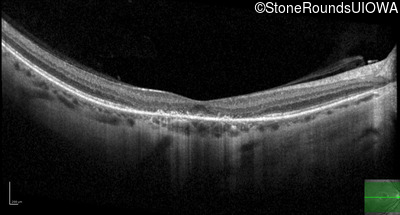

Age at visit: 40 years

OD OS

This 40 year old woman first noticed a reduction of her visual acuity about two years ago. She has been sensitive to light for as long as she can remember.

Age at visit: 41 years

Diagnosis & molecular findings

Disease Gene Allele 1 variant(s) Allele 2 variant(s) Inheritance mode

AD Stargardt Disease PROM1 Arg373Cys CGC>TGC   AD